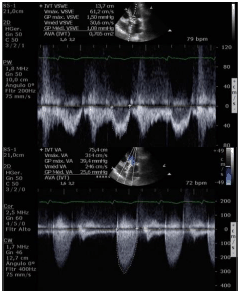

Considerando uma paciente de 87 anos, portadora de hipertensão arterial sistêmica, admitida com dor torácica e dispneia aos pequenos esforços. Ao exame: PA = 110 x 80 mmHg e FC = 72 bpm, nota-se sopro sistólico em foco aórtico 3+/6+, mesosistólico e A2 reduzido. ECG com ritmo de FA e sobrecarga ventricular esquerda. Ecocardiograma com cúspides espessadas e restrição na abertura.

Analise as imagens e dados abaixo:

- Superfície corporal = 1,9 m2;

- FE 2D = 56%;

- Septo = 14 mm;

- Parede posterior = 13 mm;

- PSAP = 40 mmHg;

- Volume AE = 54 ml/m2;

- VSVE = 2,2 cm;

- IM moderada e IAo leve;

- Gradiente VE/Ao máximo = 39 mmHg e médio = 25 mmHg;

- VTI VSVE = 13 cm, VTI AO = 75 cm.

Com base nesses dados e imagens, é correto afirmar que trata-se de estenose